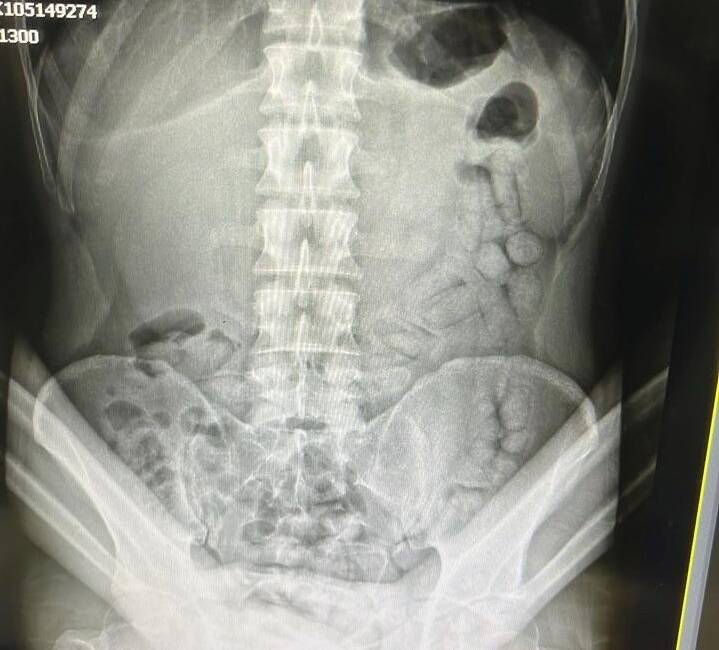

Adli makamların talimatı üzerine Gümüşhane Devlet Hastanesine götürülen şahsa yönelik iç beden muayenesinde bağırsaklarında 55 adet kapsül olduğu tespit edildi. Hastanede yapılan müdahalenin ardından şahsın bağırsaklarından çıkarılan kapsüllerin içerisinde toplamda 317,46 gram metamfetamin ele geçirildi.